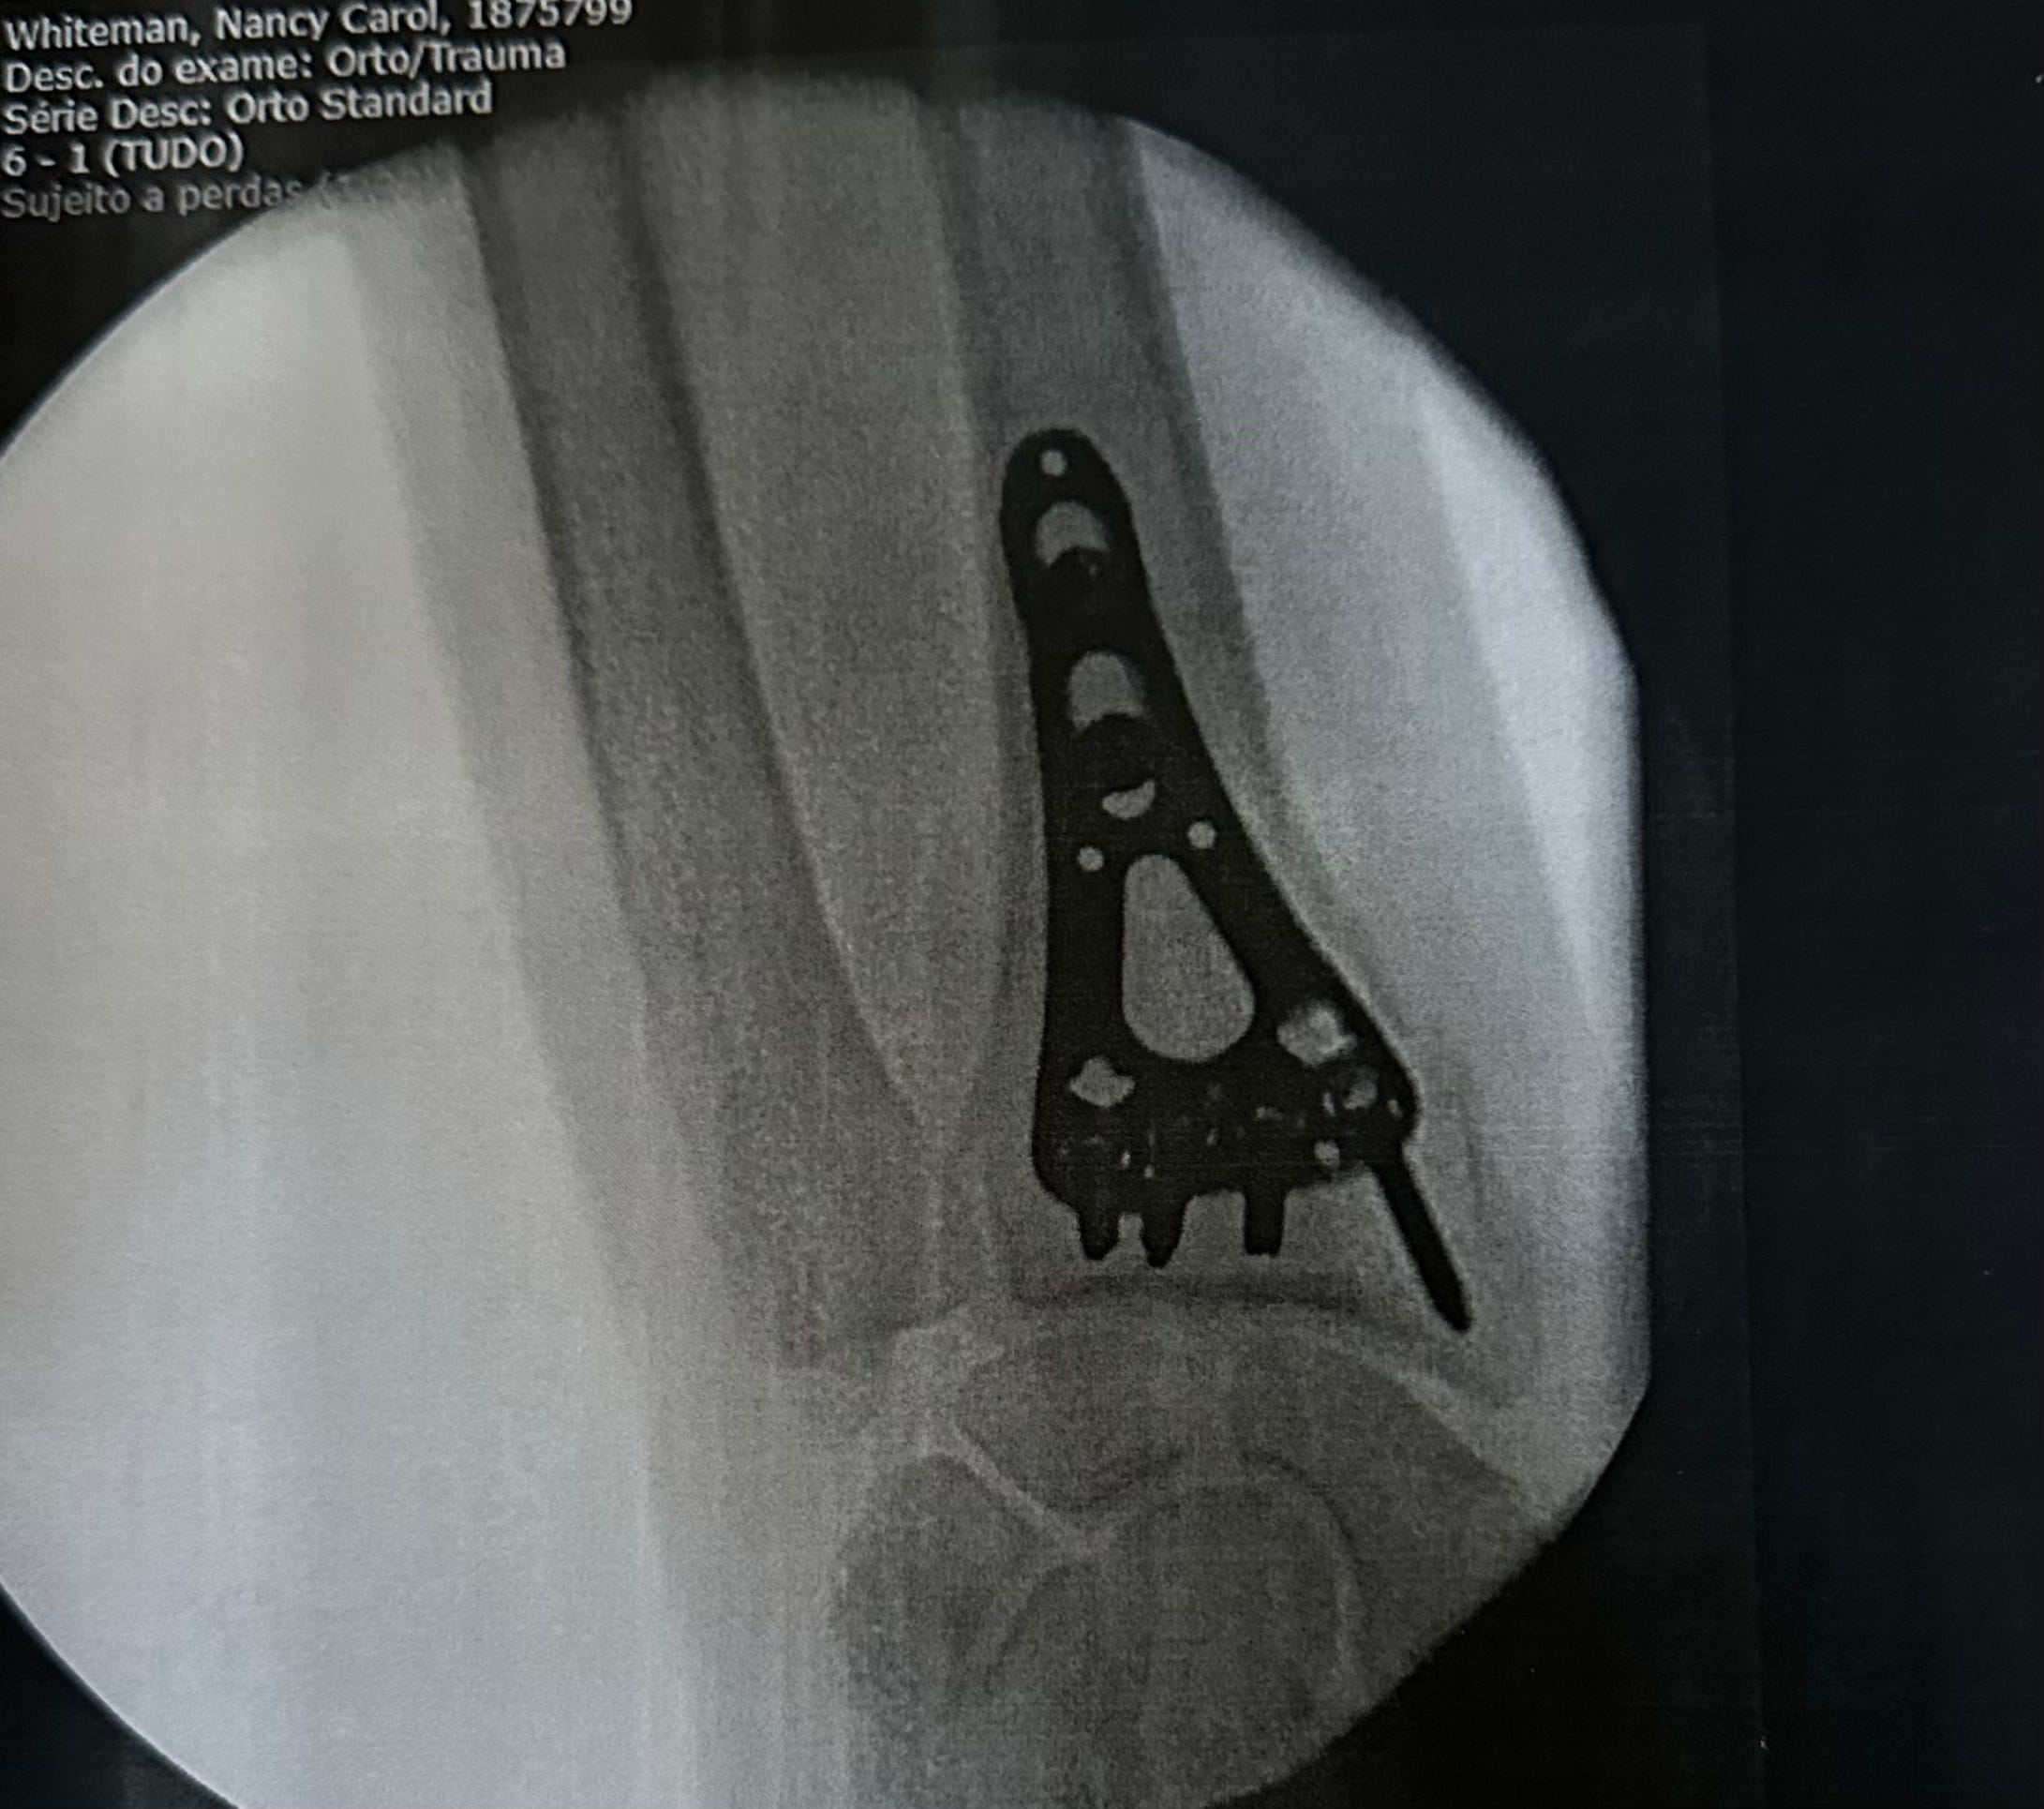

At around 18:30, they wheeled my bed to the OR. A few more questions from the anesthesiologist and off to la-la-land. Within the hour, I was waking up in post op in the bed I had arrived in. I was taken back to my room and told they would give me tea and cookies at 07:00 and disconnect the IV so I could get up. And that is exactly what happened.

Dr Maria appeared at 9:00 to check on me. She explained that her associate, who had assisted with the surgery, would see me the next day at the VRSA clinic. She had completed her discharge papers, and as soon as the nurse removed the IV from my arm, I was free to go. She also provided me with the photo above. I called Denise, and within 2 hours, I was home again.